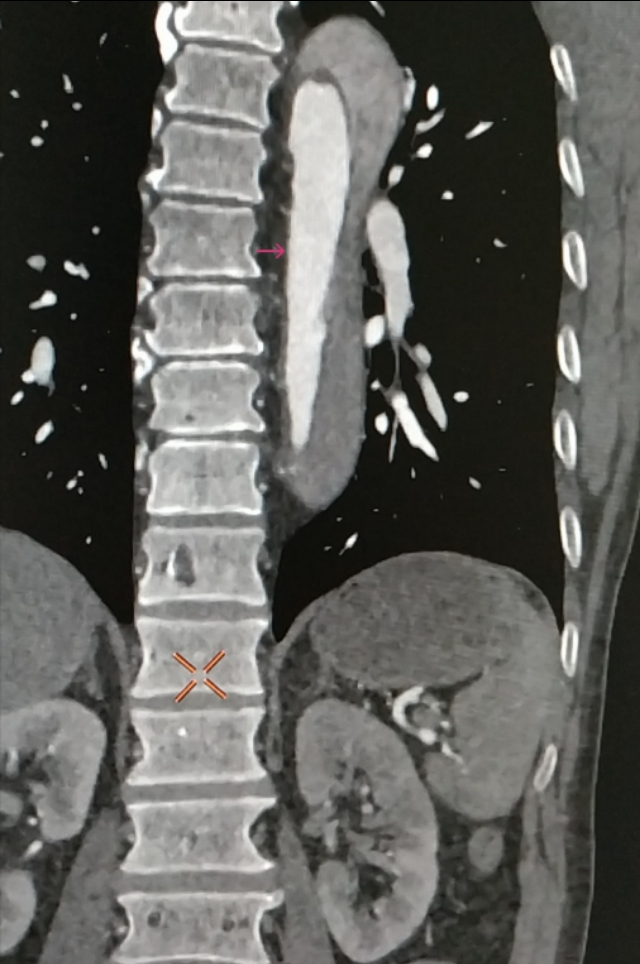

感觉不像,于是带着疑问,跟家属沟通好,我们给患者做了肺动脉和主动脉的全层CTA,发现是那个隐藏已久的杀手——主动脉夹层。而且,是全层撕裂,如下图。

咱们再聊聊主动脉夹层这个病。主动脉夹层是血管撕裂性疾病,指的是人体最大的血管主动脉内膜破裂,血流在经过破口的时候进入中膜,形成真假两腔,类似于双层水杯,类似于轮胎鼓包,这样的一种疾病。死亡风险极其高,多数病人有突发的胸痛,也可以各种症状出现,临床迷惑性极强。

因此,既然是血管内膜的破裂,由于血管的生理保护机制,血小板就会出现聚集进行止血,凝血系统也会被激活参与止血,形成血凝块,只是这种血凝块发生在我们的大血管上,跟我们的手磕破了发生的过程一样。而体内另一个系统——纤溶系统为了对抗凝血也会分解掉一部分血栓变成D-二聚体产生抗凝的效果,只是效果比较弱而已,于是,凝血与血栓分解就这样动态平衡着,直到某一方战胜另一方(出血、凝血、纤溶三者动态平衡相互制约)。